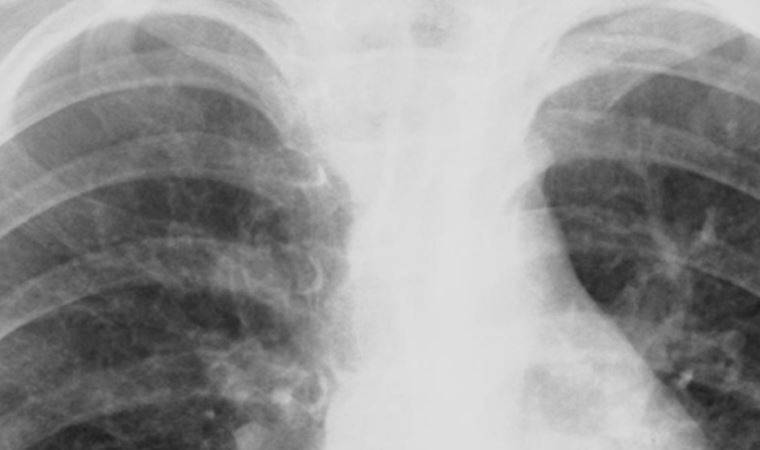

Uzmanı uyardı: 'Köprücük kemiği kırıkları ciddi sorunlara neden olabilir' Uzmanı uyardı: 'Köprücük kemiği kırıkları ciddi sorunlara neden olabilir' 30 yaş altı genç ve aktif spor yapan erkeklerde daha sık görülen köprücük kemiği kırıklarına karşı uyaran Op. Dr. Merdan Artuç, “Köprücük kemiğinin üzerine düşülmesi sonucu bir kırılma sesi duyulabilir. Ardından ağrı, şişlik ve şekil bozukluğu görülebilir. Beraberinde aynı taraf kürek kemiği kırıkları, kaburga kırıkları ve damar sinir yaralanmaları olabilmekle birlikte akciğer delinmesi gibi durumlar da olabilir” dedi.